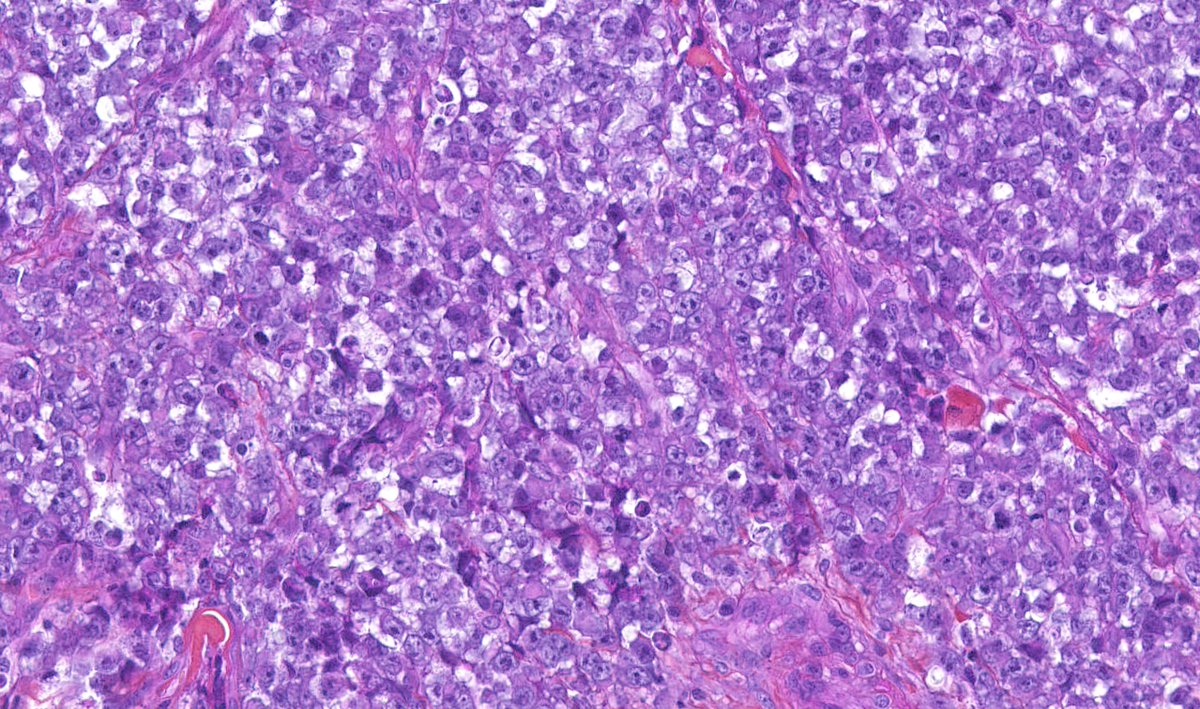

Malignant cutaneous myoepithelioma : ulcerated skin neoplasm - plasmacytoid, epithelioid, spindle & small undifferentiated cytology - chondroid matrix - high mitotic activity (>15.mm2) - geographic necrosis #dermpath #bstpath